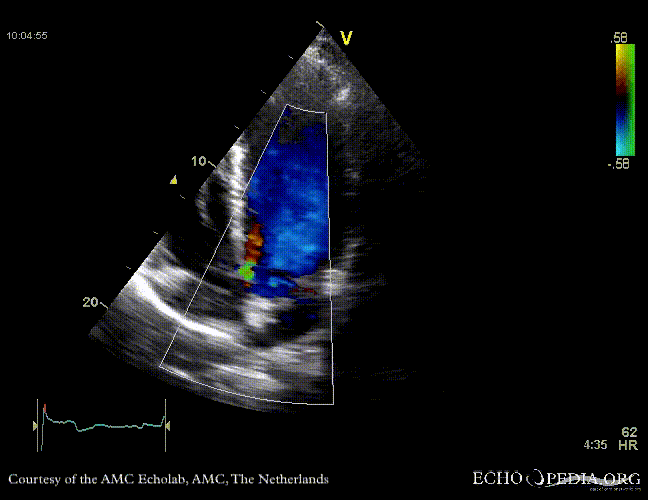

Case 10